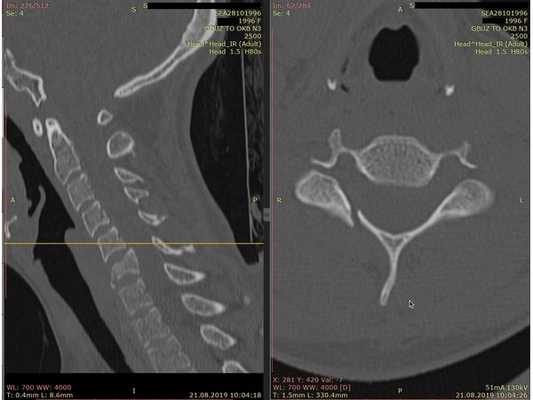

- Компьютерная томография шейного отдела позвоночника: выявлен компрессионно-оскольчатый перелом тела 6-го шейного позвонка (С6) и его дуги справа.

Контрольная КТ шейного отдела позвоночника на уровне тела позвонка С6. Виден установленный кейдж из пористого никелида титана и фиксирующая шейная пластина.

- Сформировали имплант из пористого никелида титана и установили между телами позвонков С5 и С7.

- Установили шейную пластину и зафиксировали 4 винтами: по 2 винта в тела позвонков С5 и С7. Выполнили рентген для контроля.